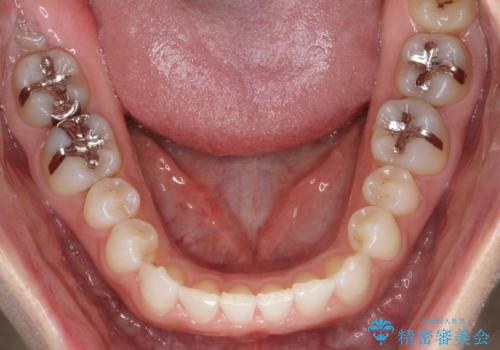

- 前歯の正中離開(すきっ歯)の改善を希望され来院された患者様です。

初診時の歯並びの状態としては、上顎中切歯間に1mm程の隙間があり、その他に見た目に関して気になるような問題点はない状態でした。

インビザライン(マウスピース)にて上顎のみの矯正治療を行いました。

見た目、嚙み合わせ及び、治療期間や施術内容に大変ご満足いただきました。